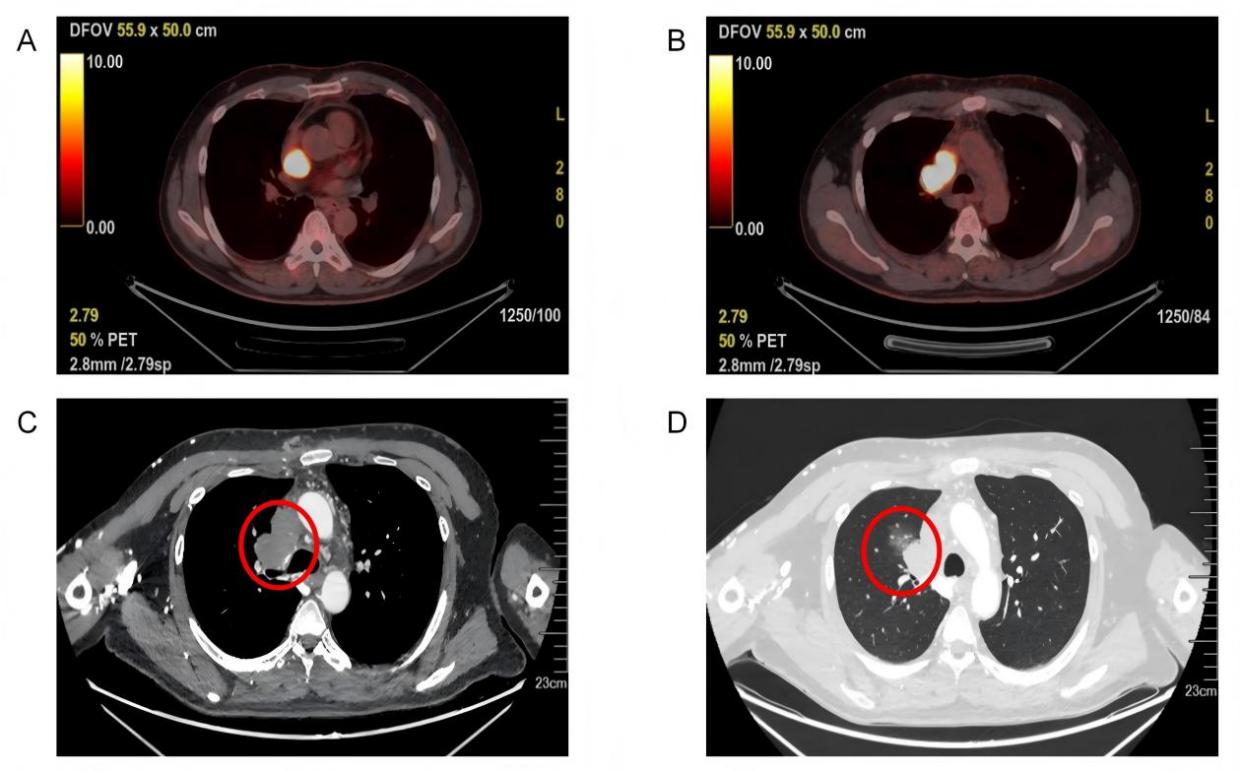

A:肿瘤侵占右心房;B:肿瘤堵塞上腔静脉;C:肿瘤压迫右主支气管;D肿瘤侵犯右侧肺门